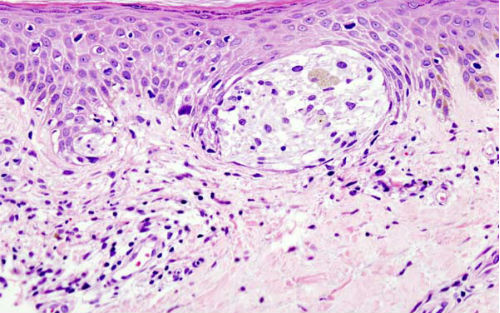

在经遗传改造、肿瘤细胞能够生成带有一种发光标记物的tEVs的小鼠中,研究人员证实tEVs可以离开肿瘤,迁移至全身,并发现它们大多数高度集中于附近的淋巴结处,这些tEVs是通过淋巴管运送到此处的。在另一组携带不同受体蛋白的黑色素瘤小鼠中,研究小组发现tEVs主要与SCS巨噬细胞互作,SCS巨噬细胞在环绕淋巴结的纤维包膜内直接形成了一个细胞层。

为了确定小鼠中的观察结果与人类疾病是否相关,研究人员检测了来自13名黑色素瘤患者的无癌前哨淋巴结——它们最靠近肿瘤,预计肿瘤最早扩散至此。尽管已经证实了这些淋巴结自身没有黑色素瘤,研究人员却在90%患者淋巴结周围的SCS巨噬细胞中发现了黑色素瘤源性物质。在这些巨噬细胞中存在的肿瘤源性物质并未反映原发肿瘤进展情况。